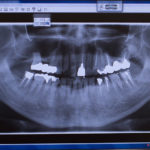

大分県でインプラント治療を受けるとき、費用面だけではなく通院回数や通院期間がどのくらいかかるかも気になっていると思います。「インプラントで普通に食事ができるまで、結局どれくらいの期間がかかるんだろう……」と疑問をお持ちではありませんか?インプラント治療は1日で終わることはありません。インプラント土台を歯茎の中に埋入し、骨とインプラント体が結合するのを待ちます。治療をスタートしてから日常生活に戻れるまでどのくらいの期間がかかるのか気になるかと思います。実際インプラント治療にかかる期間は個人差があり、口内の状態などにより期間は大きく変わります。大分県でインプラント治療をお考えの方へ一般的な目安ではありますが、治療を受けようか迷っている方はぜひ参考にしてください。

インプラントの治療期間は、あごの骨を増やす手術の有無や手術方法、口腔内の状態などにもよりますが大体2~3か月から、長い場合1年ほどかかることもあります。また、手術をした翌日以降は傷口の確認や抜糸のための通院が必要となる場合もあります。インプラント治療では1回法と2回法の手術方法がありお口やお身体の状態をみて、どちらの方法が適しているか歯科医師が診断します。どちらの方法が優れているということはないのが現状です。